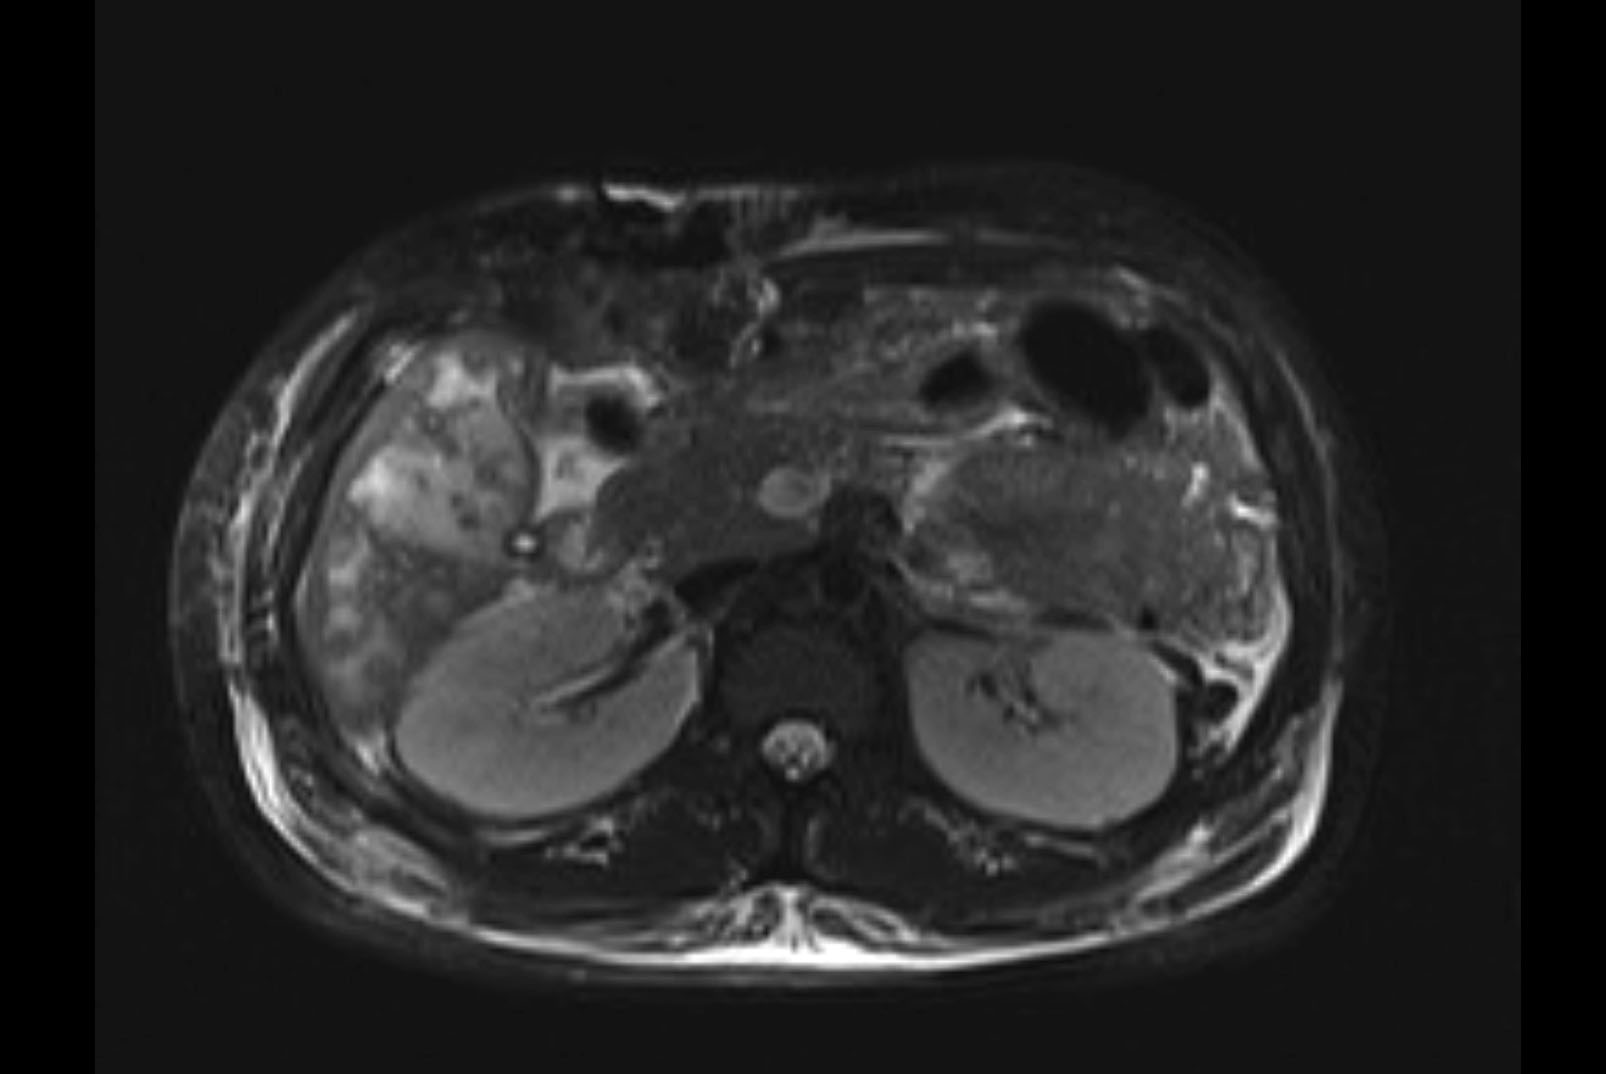

MRI T2